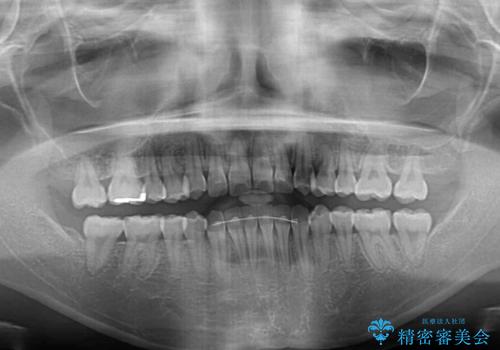

- 前歯のデコボコとクロスバイトを治したいとのことで来院された患者様です。

上下顎ともに歯列全体の側方拡大とIPR(歯と歯の間を削る)によってデコボコとクロスバイトが解消するように設計し、インビザラインにより治療を行うこととしました。

下顎骨の左側への骨格的なずれが強く、上下の正中の位置合わせや奥歯の咬み合わせ構築に苦労しました。